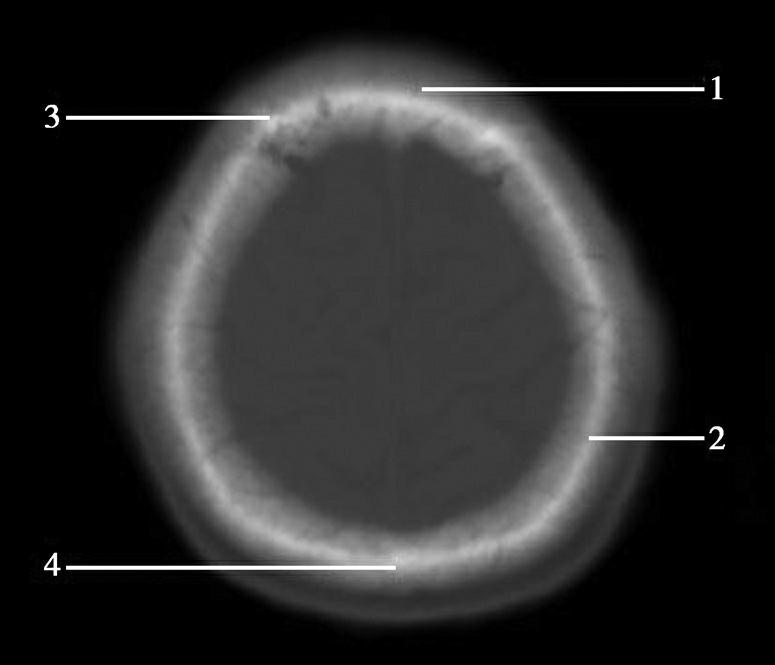

Alberta卒中项目早期CT评分(Alberta stroke program early CT score,ASPECTS)是一种评价急性缺血性卒中患者大脑中动脉供血区早期缺血性改变的简单、可靠、系统化的方法,是常用的脑卒中评定量表之一,可对缺血性病变快速进行半定量评价,有助于判定溶栓效果和远期预后。该评分主要基于CT平扫,具体分区如下(图1-2-76)所示,即选取大脑中动脉供血区2个层面。分区后共10个区域,每个区域记1分。评分时任何区域只要有低密度灶,则扣除该区域得分。正常脑ASPECTS评分为满分(10分),若MCA供血区广泛梗死累及全部区域时,则ASPECTS评分为0分。

图1-2-76 ASPECTS评分脑组织分区

A.在基底节层面(即丘脑和纹状体平面),分为各级分支M 1 、M 2 、M 3 、岛叶(缩写I)、豆状核(缩写L)、尾状核(缩写C)和内囊(缩写IC)后肢等7个区域;B.在基底节以上层面(基底节层面上2cm),包括M 4 、M 5 和M 6 。